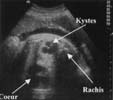

L'échographie met en évidence une masse intra-thoracique [7] :

Le doppler couleur ne retrouve pas de flux à l'intérieur de ces kystes. Il ne retrouve pas non plus de vascularisation aberrante provenant directement de l'aorte.

A ces signes directs peuvent s'associer :